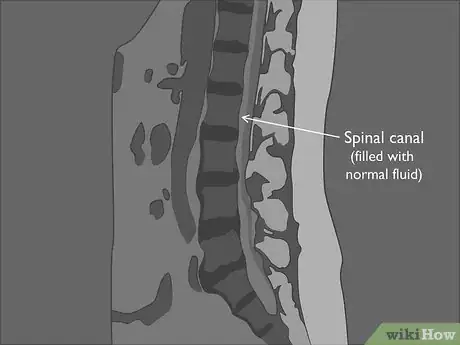

2Identify the type of MRI used in each image. At a minimum, you'll have a sagittal lumbar MRI, which is a vertical image that looks at your spine from the side. You may also have axial images, which look at a cross-section of an individual disc. Think of these as similar to slicing a tree log in sections to look at the rings on the tree. Each of these uses one of two imaging techniques:[3]

- T2-weighted images brighten the cerebrospinal fluid of your spinal canal, making it easier for your doctor to see different types of infection that might be missed by a T1-weighted image. T2-weighted images are used for both sagittal and axial MRIs.

Tip: If you see a bright, white line running down your spine on a sagittal MRI, you're looking at a T2-weighted image. The white line is the cerebrospinal fluid of your spinal canal, which holds your nerves.

3Locate the spinal canal that holds nerves and fluid. Behind the column of vertebrae and discs, you'll see a long canal that holds nerves and spinal fluid. It will either be bright white or dull gray depending on whether you have a T1 or T2 image.[8]

- If you have normal alignment, the canal will be solid, as though you could draw a straight line down the vertebrae and discs of your spinal column. The line naturally curves at the lower end of the lumbar region.